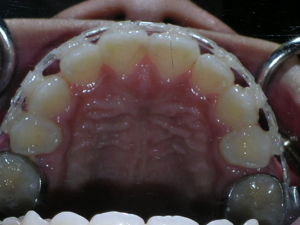

Here are the porcelain braces applied.